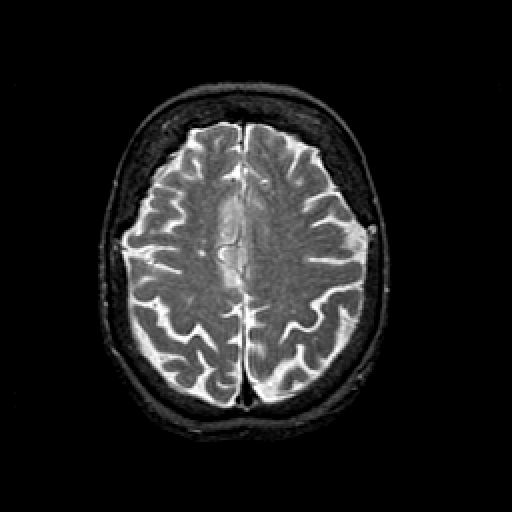

T2-weighted structural MR: Slice 39

Slice 39